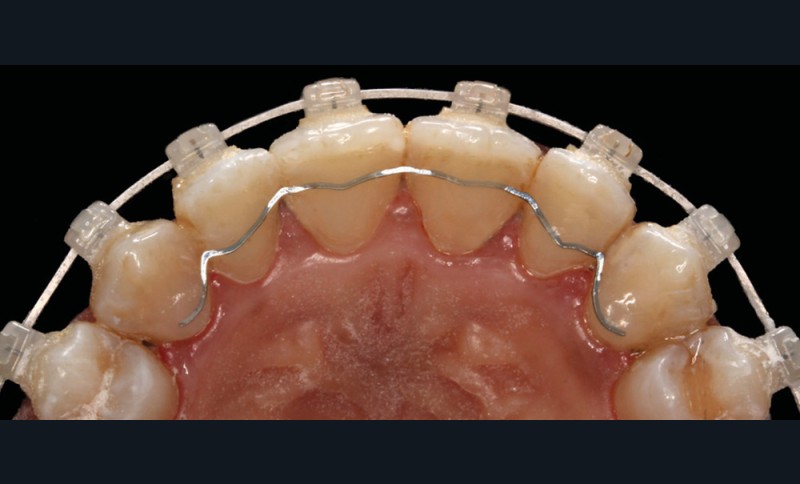

Enfin, le Pr Dierk Wiechmann décrira l’apport des nouvelles technologies au recul des limites de l’orthodontie linguale que de nombreuses recherches récentes présentent comme l’option thérapeutique la plus esthétique [4] mais aussi la plus reproductible pour obtenir un résultat individualisé de haute qualité.

Parce que les patients sont très demandeurs de dispositifs discrets, nous aborderons ensuite les techniques très prisées linguales et par aligneurs. Le Dr Jean-Stéphane Simon, une référence en technique linguale, nous montrera comment l’assistant(e) peut, par un travail à quatre mains, devenir un élément clé dans ce travail d’équipe très spécifique.

Le Dr Wajeeh Khan, fondateur d’un célèbre système d’aligneurs, présentera la technique par aligneurs et montera pourquoi, dans certains cas, il faut combiner des aligneurs et d’autres dispositifs (dont les attaches orthodontiques).

Le début et milieu d’après-midi seront consacrés à l’empreinte numérique, désormais utilisée pour les empreintes d’étude, les set-up, le thermoformage. Les Drs Guillaume Lecocq et Stéphane Desplanques monteront le thermoformage et comment ces empreintes numériques peuvent permettre de confectionner des appareils vestibulaires, linguaux, voire des aligneurs (fig. 1 et 2).